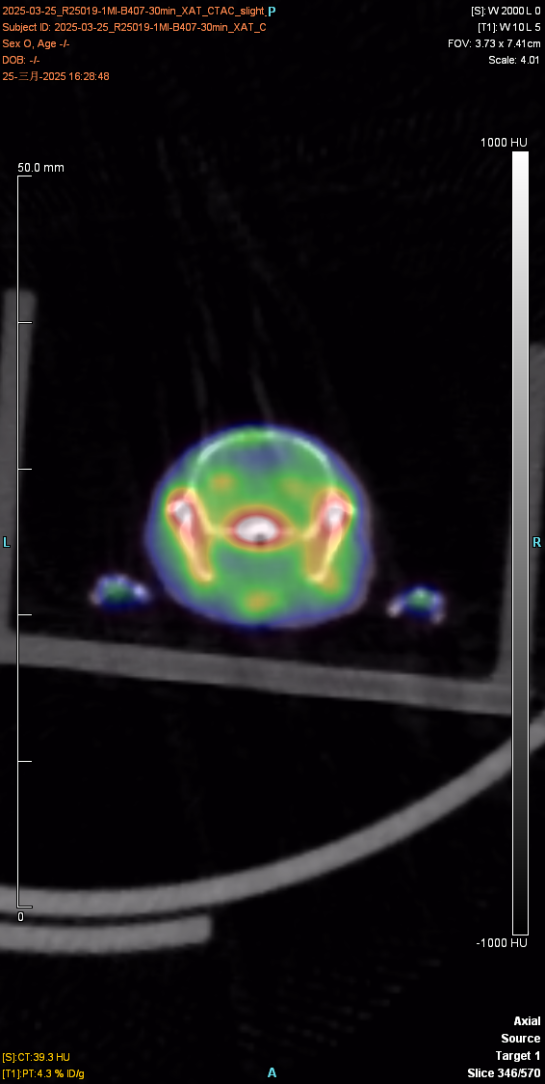

The figure below shows the 30min imaging image

The experimental animal was a mouse, provided by Huajing, with a weight of about 23g and mal♠e. After injection of the drug and anesthesia, PET scan was performed to collect images and obtain the distribution map of the drug in÷ the body. After imaging, the experimental animal gradually woke up and€ returned to normal, with good diet, two excreta and mental s£tate.